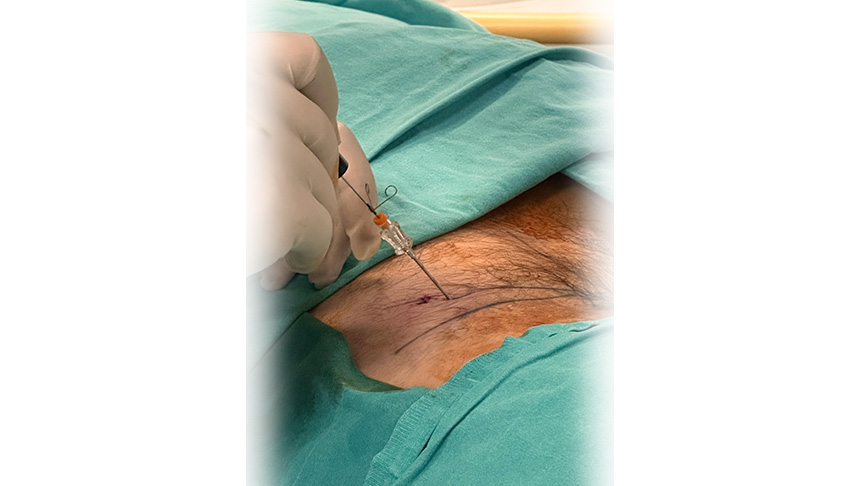

Yöntem: Uygulama lokal ve/veya sedayon anestezi altında yapılır. İşlem öncesinde skopi denilen anlık röntgen çekimi yapan cihaz ile doğru nokta belirlenir

İğne ve Ekipman: Daha sonrasında özel bir iğne veya kateter kullanılarak işlem yapılır. İğne, diskin iç kısmına yerleştirilir ve Plazma RF enerjisi ile işlem yapılır.

İşlem Süreci: Nükleoplasti işlemi total olarak (hastanın hazırlığı steril örtünmesi ve lokalizasyonun yapılıp çalışma kanülünün yerleştirilip Plazma RF uygulanması) 30-40 dakika sürer